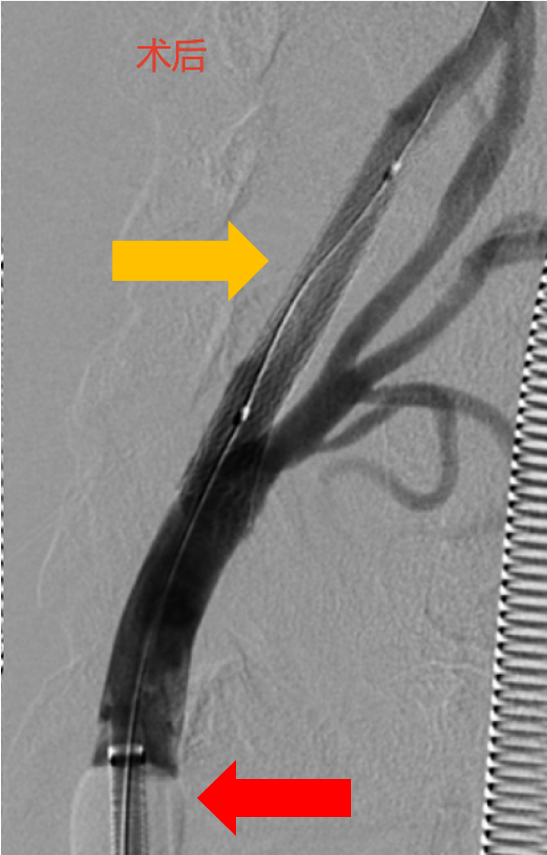

PT-CAS为颈动脉狭窄提供了更为科学、合理的腔内治疗方案,尤其是对于高位病变、不稳定斑块、严重狭窄甚至闭塞、入路条件苛刻的病例。

PT-CAS目前已成功完成了部分临床应用,取得了满意的近中期安全性和有效性,期待进一步的多中心临床研究,为患者早日带来更优的治疗方案。